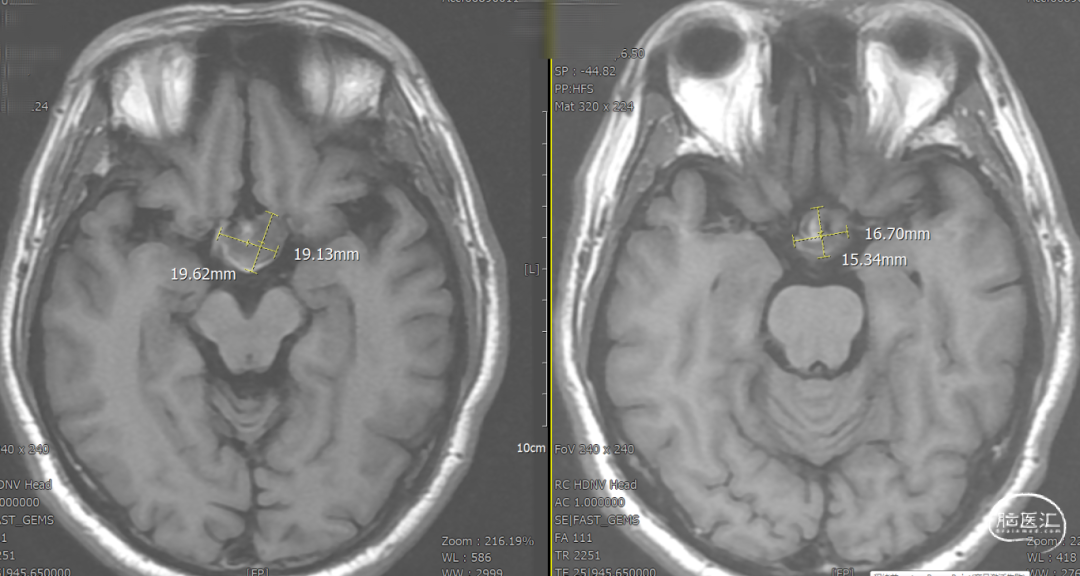

辅助检查示:2025-01-08 鞍区及垂体MR平扫:鞍内及鞍上肿瘤,垂体瘤并卒中?建议鞍区及垂体MR增强扫描。

DSA造影3D重建测量